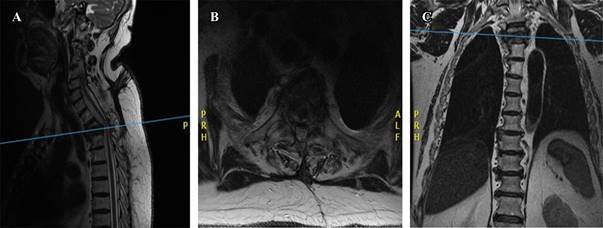

In our institution he was initially classified neurologically as ASIA C, an MRI was taken showing vertebral collapse of 70% at T2-T3 level with spinal cord compression in 40%. Postoperative changes of laminectomy from C7 to T4 levels with a high risk of instability were also observed (Figure 2). It was decided to perform a posterior fixation of C5-T6 and an anterior corpectomy by sternotomy. Once taken to the operating room under general anesthesia, posterior fixation is performed followed by an anterior approach by sternotomy. It was observed a coronary bypass at the level of the bilateral internal mammary artery as well as abundant fibrous tissue, so it was decided not to continue with this approach due to the high risk of massive cardiac infarction during the procedure. The wound was closed with wire cerclage. For this reason, the surgical plan was changed to a right infraclavicular thoracic approach.